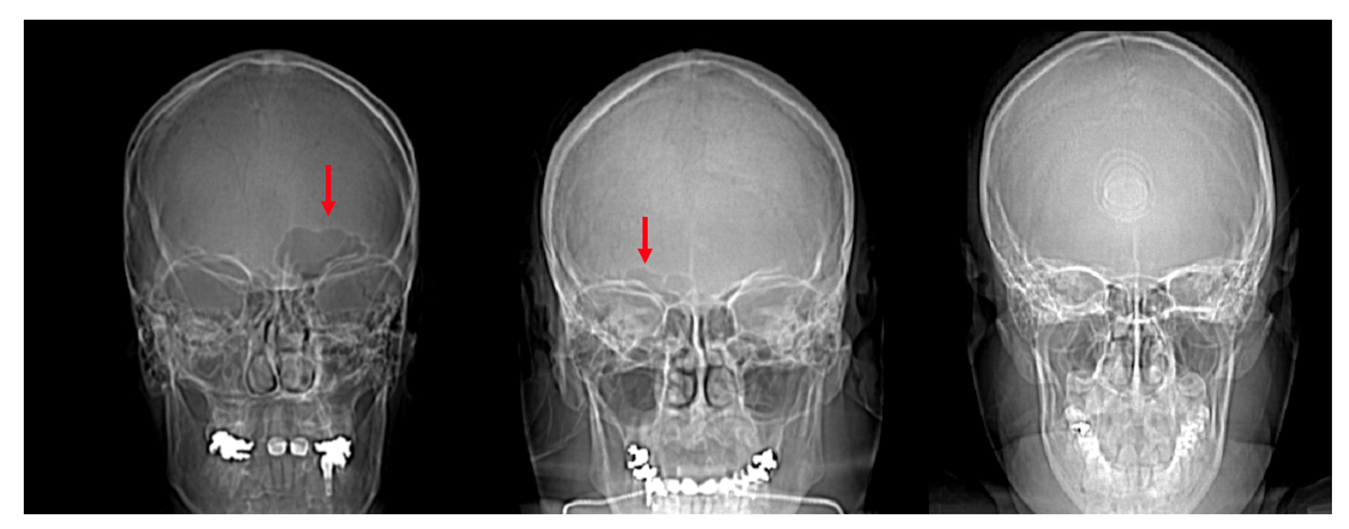

The frontal sinus was absent in 12 individuals (3.7%) and six (1.8%) lacked a frontal sinus that intersected medially. As described above, this reduced the sample to 307 individuals for the morphological analyses (see Table 1). The individuals lacking a frontal sinus included three African-derived AFABs, two European-derived AFABs, two Latin-American derived AFABs, two Asian-derived AMABs, and two European-derived AMABs. Additionally, out of the 325 individuals assessed, 39 (12.0%) had unilateral frontal sinuses. There were 29 individuals (74.4%) that had frontal sinuses developed on their left sides and 10 individuals (25.6%) who had sinus development on the right (Figure 6). There were no significant differences between left and right presentations vs. assigned sexes or population affinities. However, a two-sample t-test indicated that left presentations are more common than right (t = 3.7025, df = 6, p-value = 0.01006).

Figure 6.

Scout images of the crania of individuals with a unilateral left frontal sinus (left, red arrow), unilateral right frontal sinus (center, red arrow), and bilateral absence of a frontal sinus (right).